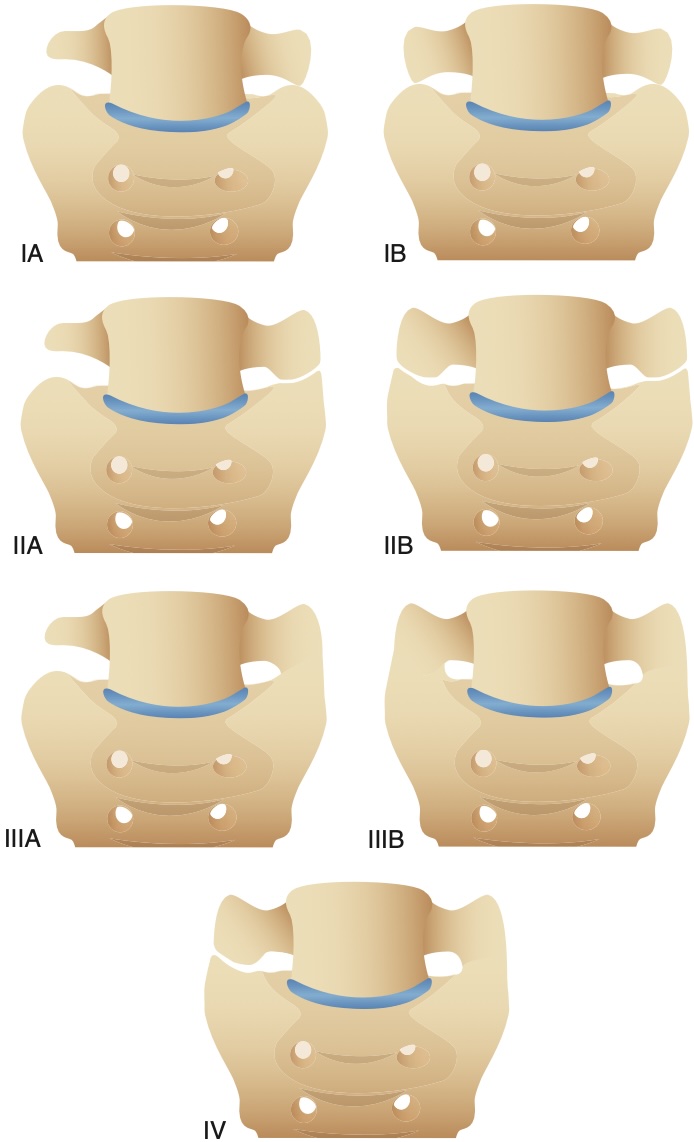

Schizas A sténose minime : LCS visible, B modérée : peu visible,

C sévère : ∅ LCS, D extrême : ∅ graisse épidurale

Castellvi I = processus transverse élargi ≥ 19 mm d'axe craniocaudal,

Castellvi I = processus transverse élargi ≥ 19 mm d'axe craniocaudal,

II = pseudo-articulation avec le sacrum, III = lombalisation ou sacralisation complète, IV = II + III